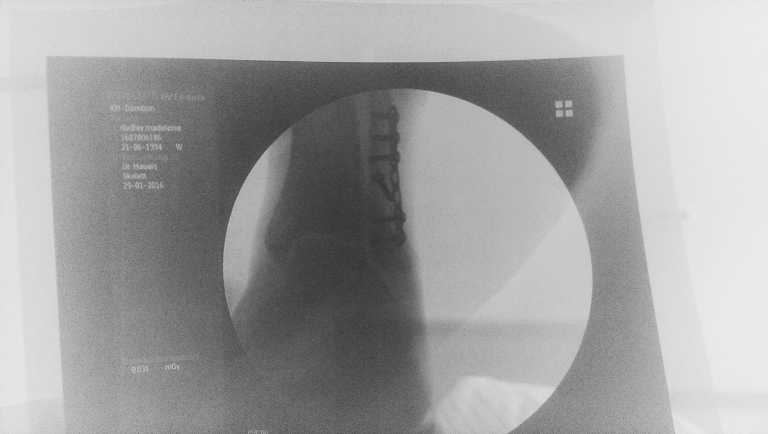

I went to the hospital a few days this week including having my operation at 7am on Friday. Selina caught the bus with me and stayed with me til I went in and then I woke up to Maddy being there at about 1. She took me home at about 4 and did her homework at our kitchen table. Seriously, I haven’t been left alone for a minute and it’s been so lovely. The operation went well, all to plan. Have some secondary problems involving the strength of my bones (ie not so strong at all apparently) but that’ll be discussed Monday when I pop back in.